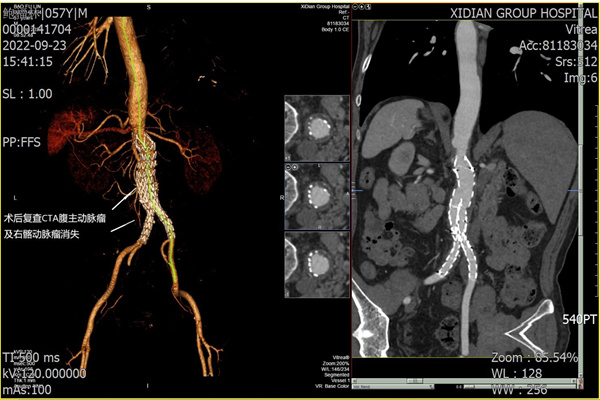

圖3:術(shù)后即刻造影圖

術(shù)后張叔恢復(fù)順利,未出現(xiàn)下肢缺血、截癱、 腸道缺血等并發(fā)癥。術(shù)后1周,復(fù)查腹主動(dòng)脈CTA,動(dòng)脈血流通暢,支架形態(tài)良好。

圖4:術(shù)后1周復(fù)查CTA